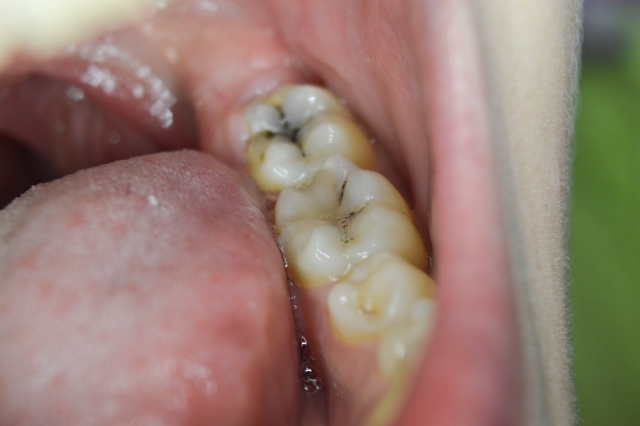

The traditional techniques to remove deep carious lesions approaching the pulp is to remove all the soft, demineralized dentin in one visit. The caries may also be totally removed using a two-step procedure, where caries is removed in stages over two visits, up to several months apart, to allow pulp time to form reparative dentin, thereby reducing the risk of pulp exposure.

Numerous clinical trials demonstrate the benefits of minimally invasive caries removal, with partial removal in symptomless teeth significantly reducing the risk of pulpal exposure.1,4,5 In one- or two-step incomplete caries removal, some caries close to the pulp of the tooth is left in place; unfortunately, there doesn’t appear to be any research that indicates how much caries should be left in place in incomplete procedures. There is additional evidence that a single one-step incomplete evacuation reduces the risk of failure, compared with two-step incomplete procedures.5

The systematic reviews found there was no advantage to complete vs. incomplete caries removal, with an overall reduced risk of pulpal complications and failures after incomplete compared with complete evacuation of the caries.1–5 Using one- or two-step partial caries removal showed success rates of over 95% up to three years and approximately 80% at five years, with partial caries removal likely more effective than step procedures at preserving tooth vitality.2